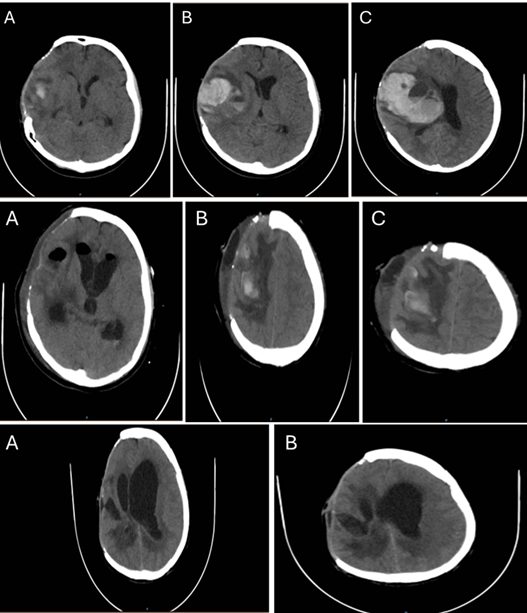

Hidrocefalia por Neurocisticercose em Aqueduto Cerebral: Relato de Caso

Felipe Meireles Dória, Lívia Novaes Teixeira, Matheus Costa Freitas, Isabella Versiani Martins Rocha, Raquel Cordeiro Mendes, Bárbara Bastelli

bjcr148